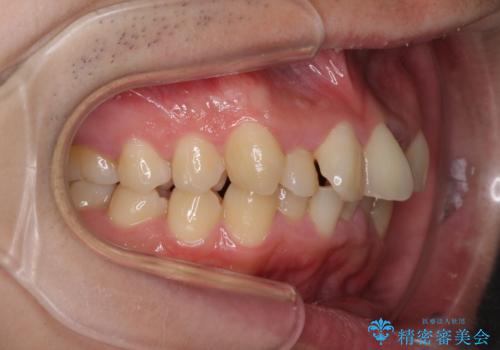

強い咬み込みですり減った前歯 デコボコを抜歯矯正で整える

口元の突出感はないものの、上顎前歯のデコボコが著しかったため、上顎左右第一小臼歯2本を抜歯することとしました。

咬合力が非常に強く、抜歯したスペースがなかなか閉じないであろうことは予想できましたが、思っていた以上に期間がかかりました。

前歯のすり減りも著しかったため、仕上げの位置の調整にも期間を要しました。